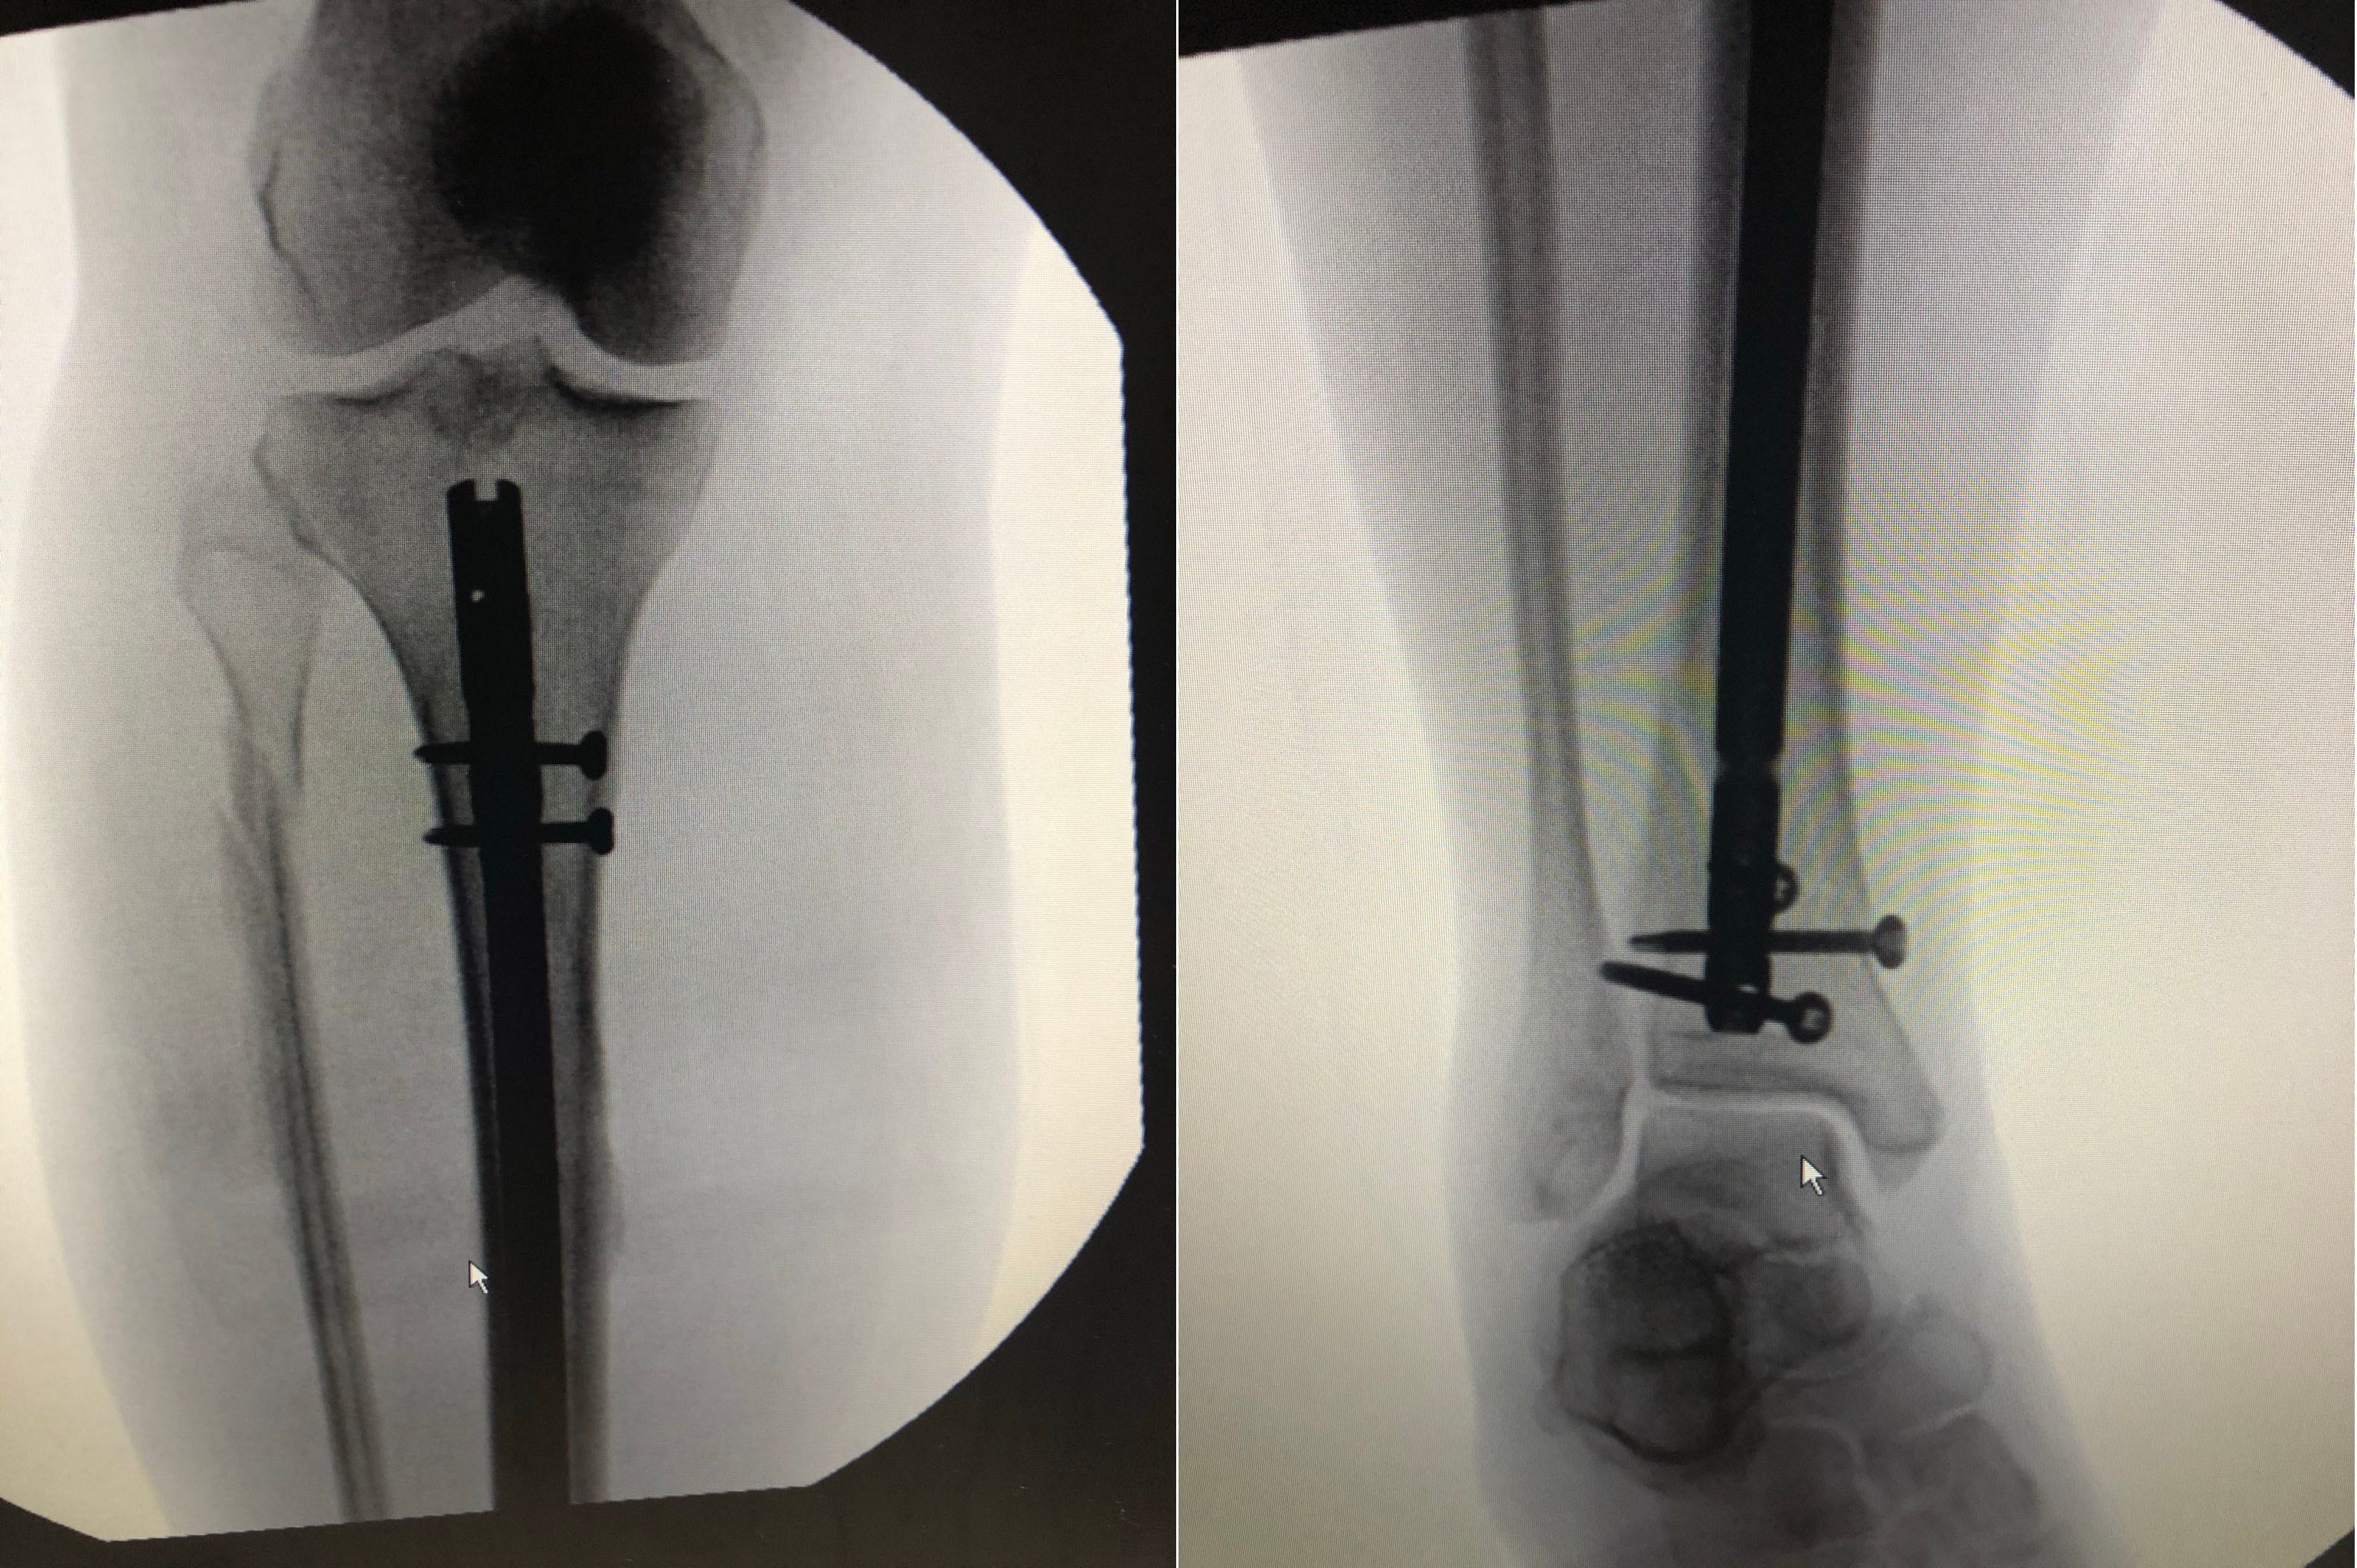

Finally, I was taken by ambulance to a Boston hospital for the surgery, and spent another three days in recovery before going home with a titanium rod and screws holding my bones together.